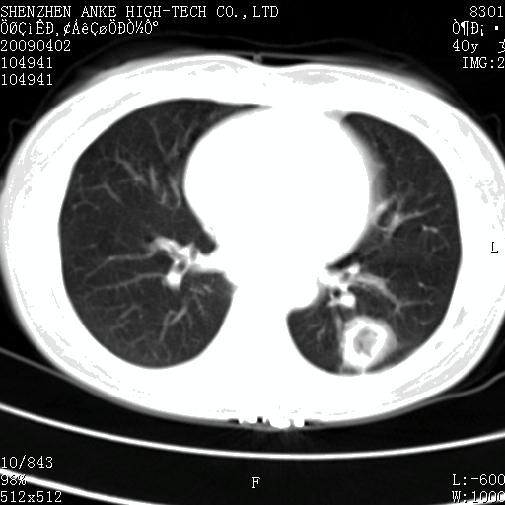

以下是引用随光逐影在2009-4-2 12:16:00的发言:[br]考虑左肺下叶背段继发性肺结核,结核球形成;建议追踪复查。

以下是引用gudu医生在2009-4-2 11:27:00的发言:[br]周围型肺癌

以下是引用卜一在2009-4-2 13:31:00的发言:[br][br] [br] 空洞壁厚不均 胸膜凹陷征。周围型肺癌可能 不排除干酪坏死型肺结核及坏死性肉芽肿。 [br] [br]支持!

以下是引用ct诊断高手在2009-4-2 13:04:00的发言:[br]空洞壁厚不均 胸膜凹陷征。周围型肺癌可能 不排除干酪坏死型肺结核及坏死性肉芽肿。